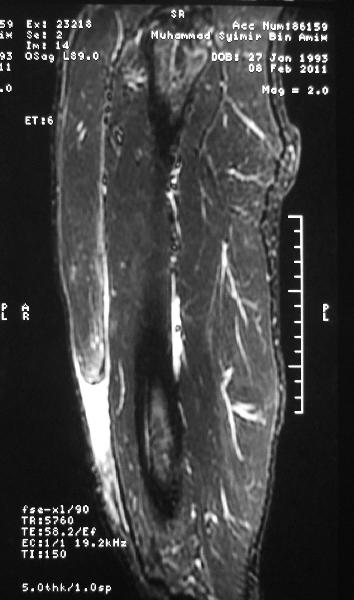

MRI scan of the left thigh was done.

It showed a complete rupture of the rectus femoris tendon with proximal retraction.